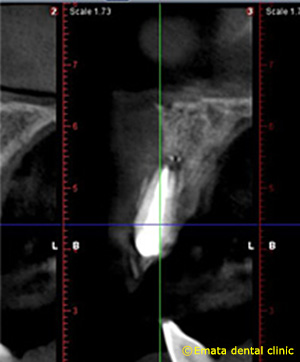

CT検査をしました。再根管治療をおこなっても、根が吸収してるので、歯が薄くなり、抜歯に近くなります。